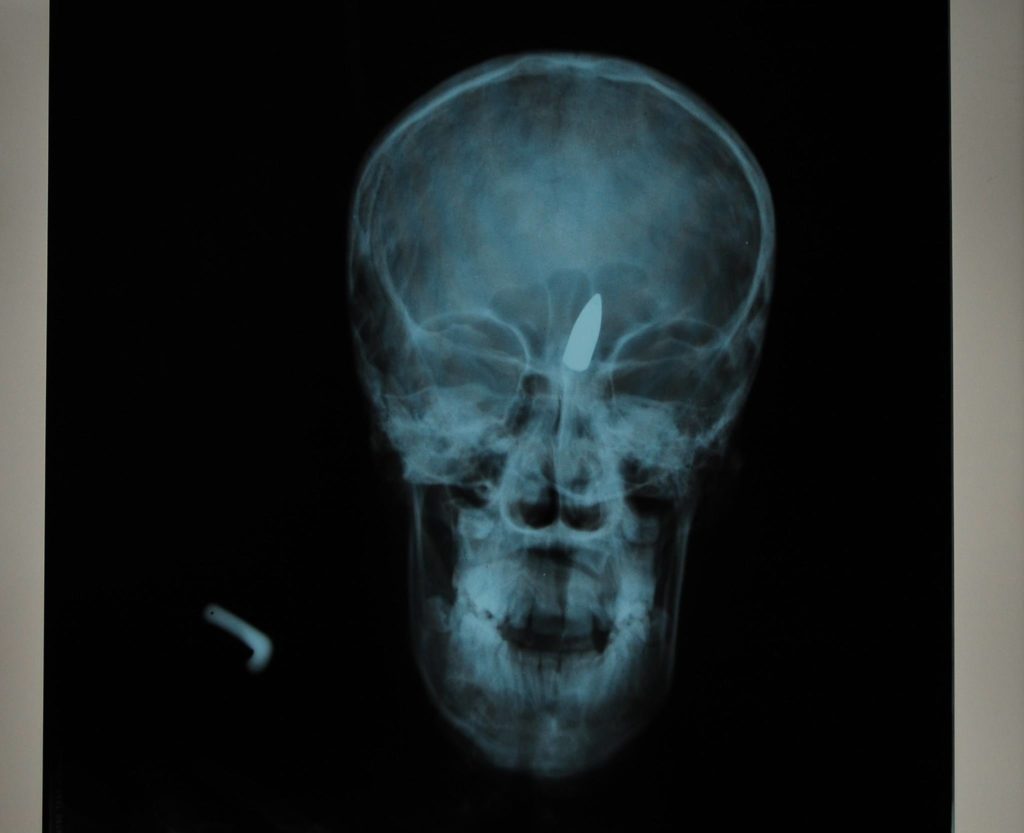

Deti sú priťahované niečím, čo by vojak, operujúci v bojovej zóne, nikdy nezdvihol zo zeme. Sú to menšie plastické predmety zhadzované z vrtuľníkov, ktoré deťom pripomínajú hračku v tvare zeleného motýľa či papagája. Nevedia, žiaľ, že opakovaným stláčaním plastického obalu sa aktivuje roznecovač. K explózii nedôjde hneď, takže dieťa si prinesie mínu často domov alebo ju ukazuje kamarátom. Výbuch prichádza neočakávane. Aj keď mína PFM-1 nie je skonštruovaná na to, aby zabila, následky výbuchu sú desivé. Deti prichádzajú o ruky, majú silné popáleniny tváre, hrudníka a často stratia zrak. Gino bol pri mnohých z nich vo chvíli, keď sa po operácii preberali z narkózy. Ako neskôr napísal v knihe Zelené papagáje, bolo neznesiteľné pozerať sa na to, ako sa jeho malí pacienti prebúdzali do tmy. „Tie zelené papagáje ich vtiahli do nej navždy.“